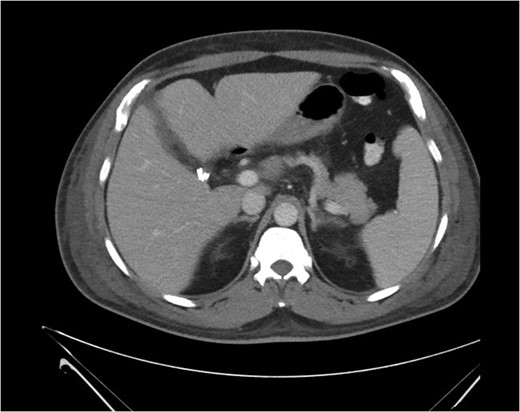

Biopsy of the affected organ is the only way to confirm the diagnosis of intravascular lymphoma. The predominant microscopic finding of IVLBCL is atypical blastoid cells with multiple mitoses that exclusively proliferate within vascular and sinusoidal structures of the organ. Mouse xenograft models have indicated that inhibition of cell migration may be involved in IVLBCL pathogenesis and may account for the limited growth locations within the host [5]. Immunohistochemical staining is positive for B-cell markers CD19, CD20, CD22 and CD79a in the absence of staining for T-cell markers [1, 6, 7]. On imaging, both primary and secondary hepatic lymphomas show mild enhancement after contrast administration including a homogeneous and rim-like pattern, and central necrosis may produce a heterogeneous appearance. Most patients with primary or secondary hepatic lymphomas also present with associated lymphadenopathy, whereas patients with IVLBCL frequently have neither central necrosis nor lymphadenopathy, presentations that may aid in differential diagnosis of IVLBCL from other forms of hepatic lymphomas [7].